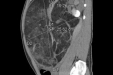

(患儿第一次手术前影像)

当时患儿已出现颅缝早闭、脑积水所致颅内压增高的危险情况,神经外科副主任医师杨明根据患儿病情,先为其做了颅缝再造手术,重塑颅骨形状,也缓解高颅压症状。第一次手术顺利完成,患儿恢复良好,但因为疾病的特殊性,一直以来患儿定期到神经外科进行随访。